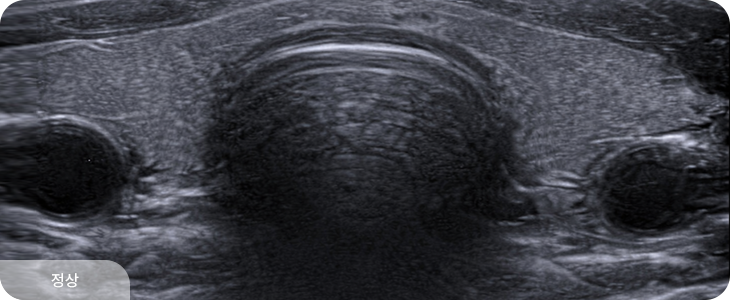

갑상선은 평소에는 잘 만져지지 않지만, 이상이 생겨 커지면 목에서 혹처럼 만져질 수 있습니다.

갑상선 질환은 결절의 크기보다,

구조적 특성과 변화 양상을 함께 살펴야 합니다.

호수유외과는 정밀 검진을 통해 상태를 정밀히 파악하여

환자 상태에 맞춘 진료 방향을 제시합니다.